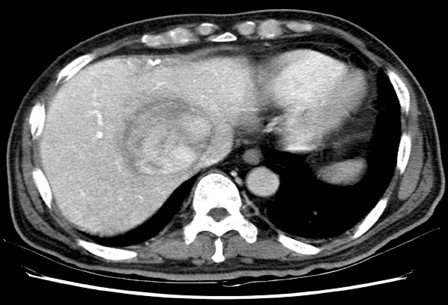

PVT diaqnozunu dəqiqləşdirmək üçün portoqrafiya aparılır – Doppler USM, KT və ya MRT angioqrafiya.

- Kontrastlı müayinələrdə damarda tromb və ya kavernoz transformasiya

- portoqrafiyada vena mənfəzində trombun görünməsi;

- venanın distalında genişlənmə və kavernoz transformasiyanın görünməsi;